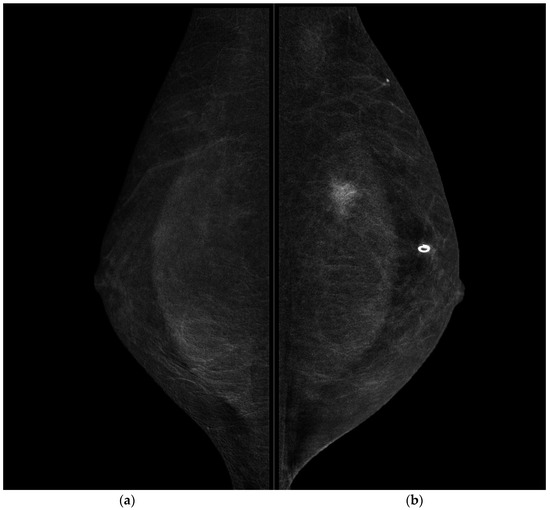

CESM showed the presence of a highly suspicious enhancement area with indistinct margins of 15 mm in the superior pre-pectoral region of the left breast, corresponding to the MR-detected lesion.

CESM also confirmed the presence of a metallic marker in the left retro-areolar breast, previously released in the breast biopsy site (Figure 1, Figure 2, Figure 3 and Figure 4).

Figure 4. CESM MLO projections of the right breast (a) and left breast (b). A highly suspicious enhancement area with indistinct margins of 15 mm in the superior pre-pectoral region of the left breast was confirmed in MLO projection.